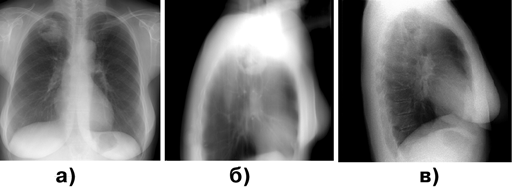

Наибольшие трудности для диагностики представляют пневмониеподобные и полостные формы периферического рака легкого (рис. 2).

Рисунок 2. Периферический рак верхней доли правого легкого, полостная форма:

а — прямая проекция; б — боковая проекция; в — томограмма